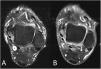

‘Signet ring sign’. Axial T2-weighted MRI images of the ankle at the level of the posterior tibial nerve with fat saturation (A) and T1-weighted images with fat saturation after administration of intravenous contrast (B). They show the lateral displacement of the nerve fascicles (arrowheads), which take on a crescent morphology, and the absence of a fatty plane interposed between the nerve and the lesion (asterisks in A and B). White arrowhead: posterior tibial nerve.

The other identifiable sign, much more specific for demonstrating their intraneural location, is the ‘signet ring sign’.5,6 In our case, this sign can be identified in the proximal portion of the lesion, where the lesion can be seen to occupy the epineurium of the posterior tibial nerve, laterally displacing the nerve fascicles and interposed fat, resulting in an image with a crescent morphology adjacent to the lesion, reminiscent of this figure. In other cases, there may be no fatty plane separating the nerve fascicles from the lesion. This sign can be identified on axial sequences, and is more likely to be identified on fluid-sensitive sequences, and after contrast administration.

In extraneural lesions, the crescent shape is not usually present, and the fatty plane between the nerve fascicles and the lesion is preserved.